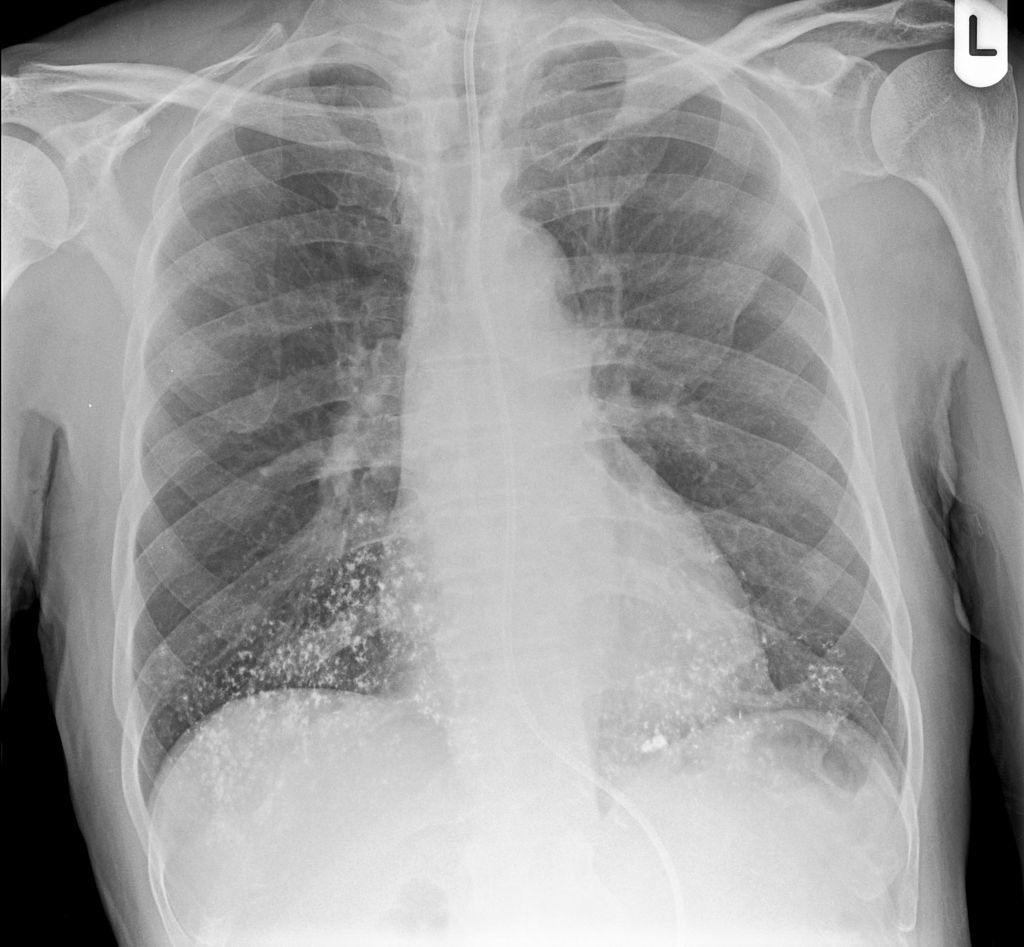

CLINICAL HISTORY:

New cough, ?NG tube position

FINDINGS:

Multiple dense radiopacities demonstrated in both lung bases suggesting aspiration of barium sulphate, I note that a barium swallow was performed yesterday.

Lungs are otherwise clear, no pleural abnormalities.

NG tube is correctly sited, safe for use.

Heart size is normal, hila and mediastinal contours are normal.

IMPRESSION:

Aspiration of barium sulphate

BACKGROUND:

Some patients may aspirate on barium sulphate during GI radiological investigations. If a patient is pre-determined as an aspiration risk then a non-ionic iodinated contrast study is usually performed.

DIFFERENTIAL DIAGNOSIS:

None

FOLLOW UP:

If new aspiration (as in this scenario) patient would benefit from chest physiotherapy assessment